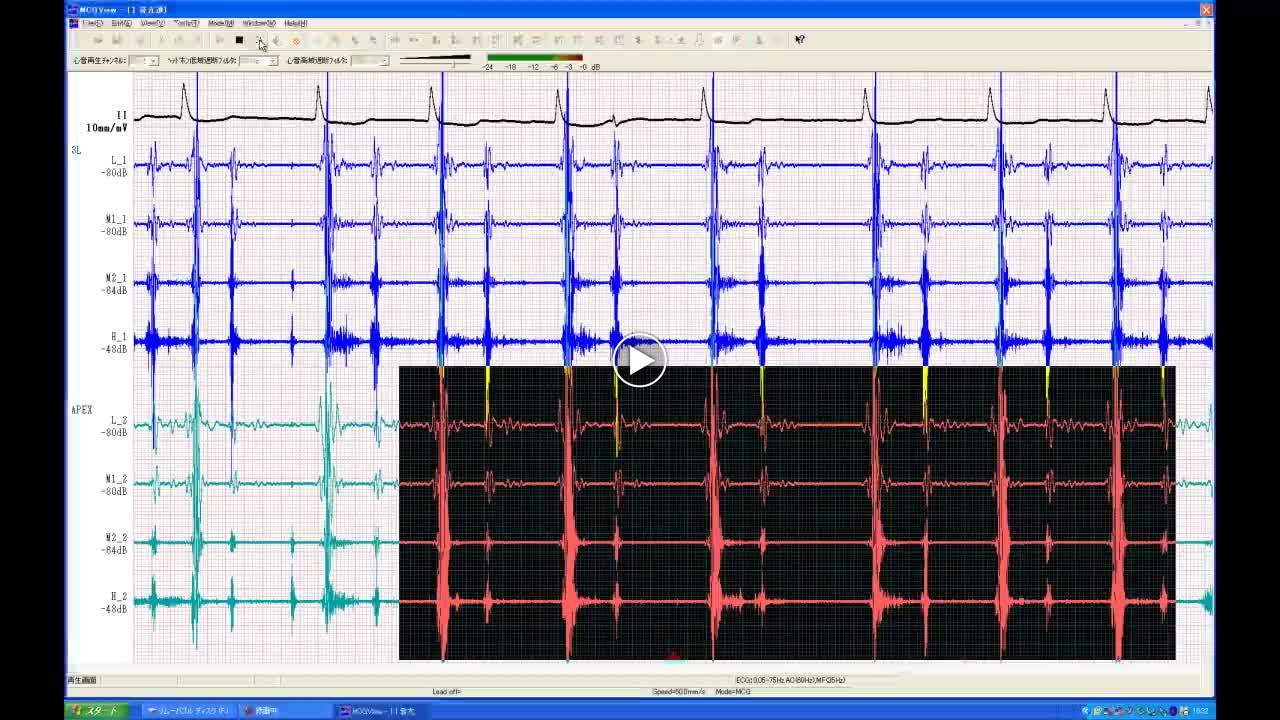

• 図5 Ⅰ音の亢進 a